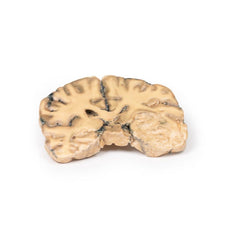

3D Printed Ruptured Berry Aneurism

Pathology

The specimen shows the basal surface of the brain. There is a saccular aneurism 5 mm in diameter at

the junction of the right internal carotid and the posterior communicating artery, which has ruptured. There is

subarachnoid blood in the immediate area in the cisterna magna and on the inferior surface of the right frontal

lobe. There is a similar unruptured aneurysm on the left side. The right frontal lobe appears softer and more

friable anteriorly